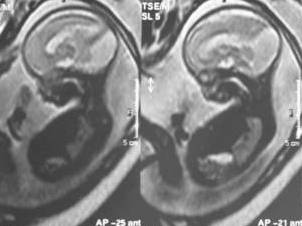

Tanı anne karnında doğum öncesinde ültrason veya MR ile konabilir (Resim 3). Tüm hastalarda mümkün olduğunda MR çekilip diğer bozukluklar da araştırılmalıdır. Tedavi hidrosefali gelişirse söz konusudur. Şant ameliyatı ve endoskopik ameliyat uygulanmaktadır (Resim 4).

Resim 3: gebeliğin 25. haftasında çekilen MR’ da anne karnındaki bebekte Dandy-Walker malformasyonu görülmektedir.